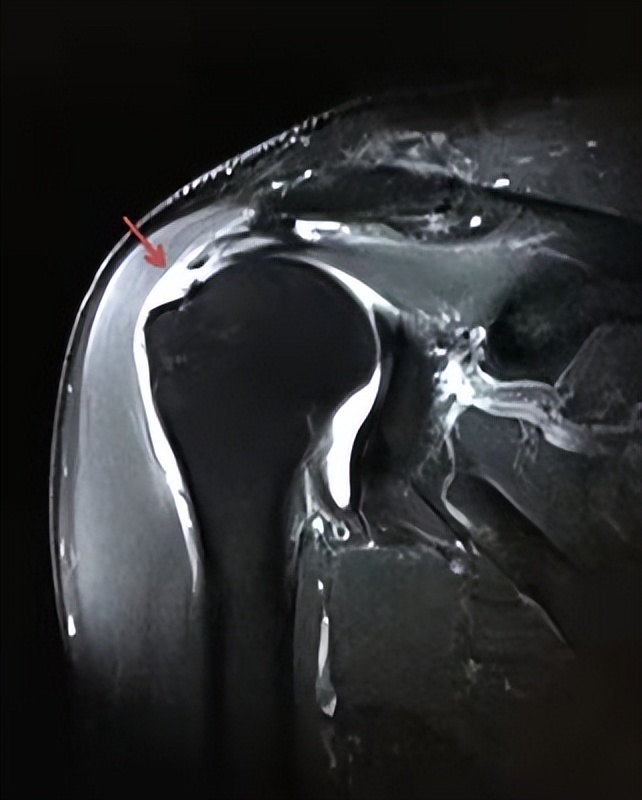

影像学:X线无异常,后期可见肌腱钙化影,MRI可见高信号水肿或肌腱信号减低影

MRI表现